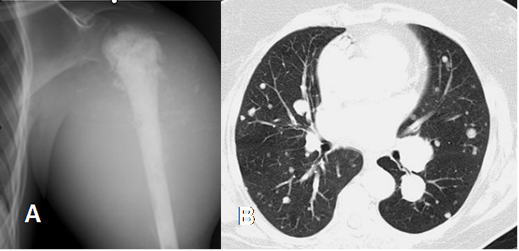

El estadiaje corporal requiere de otros estudios, como TAC de tórax y abdomen, mamografía en mujeres, gamagrafía ósea, etc, para tratar de identificar lesión poliostótica o tumor metastásico. (6). (Fig 44 y 45).

Fig 44. Estadiaje.

A: Rx AP. Masa de tejidos blandos con calcificación osteoide de la matriz, por osteosarcoma.

B: TAC axial. Múltiples nódulos pulmonares bien definidos, por enfermedad metastásica.